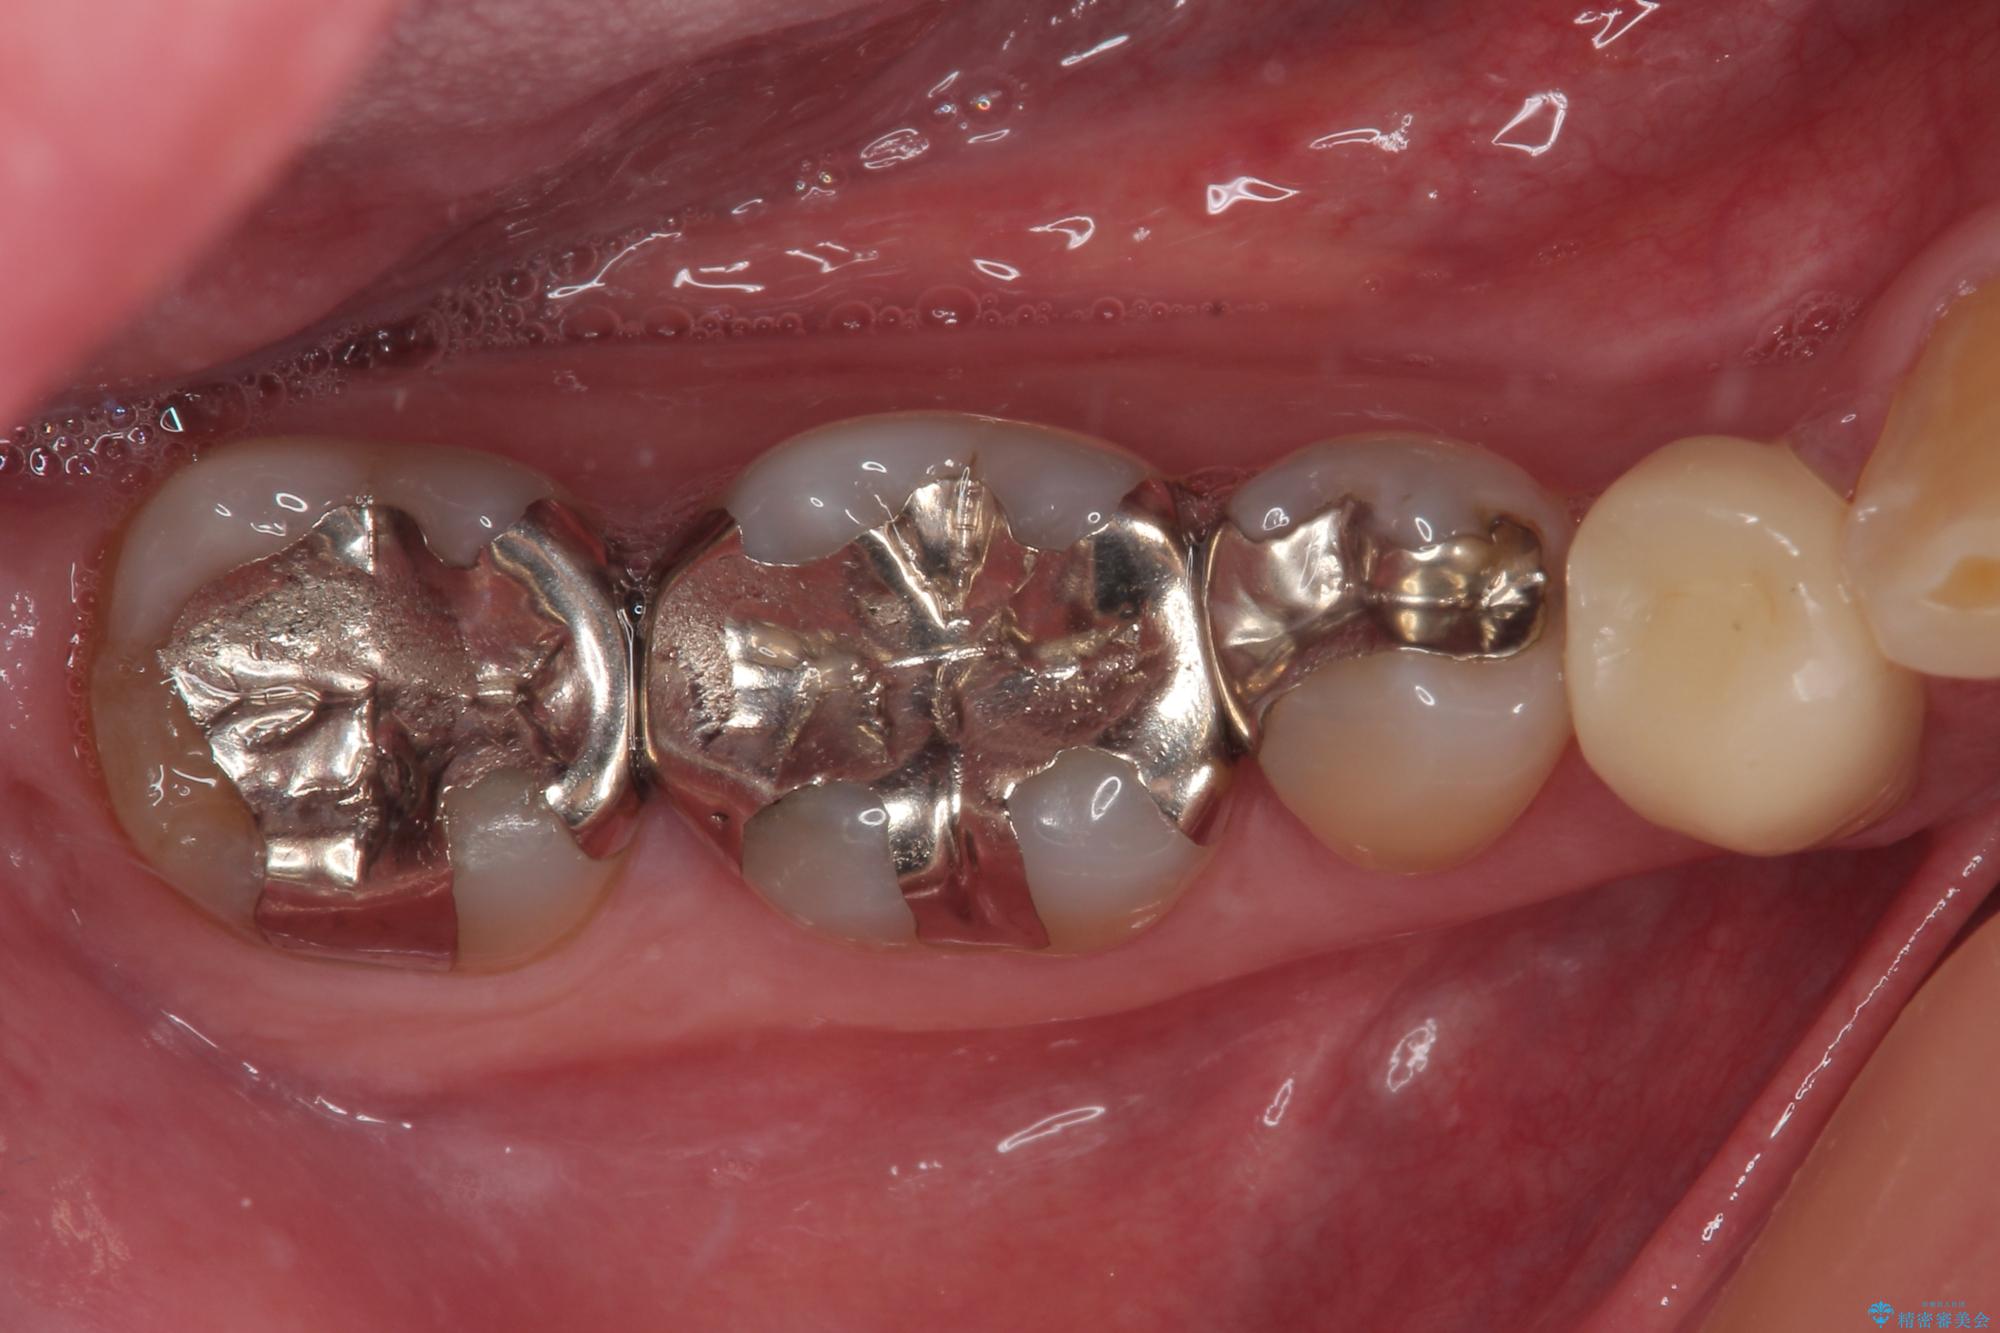

- 右下の銀歯が取れたとのことで来院された患者様です。以前にも取れていたところで、メタルインレーの不適合も認めていたため、次回外れたらオールセラミッククラウンにやり替えていくことを説明していたため、オールセラミッククラウンによる補綴治療を行っていくことにしました。